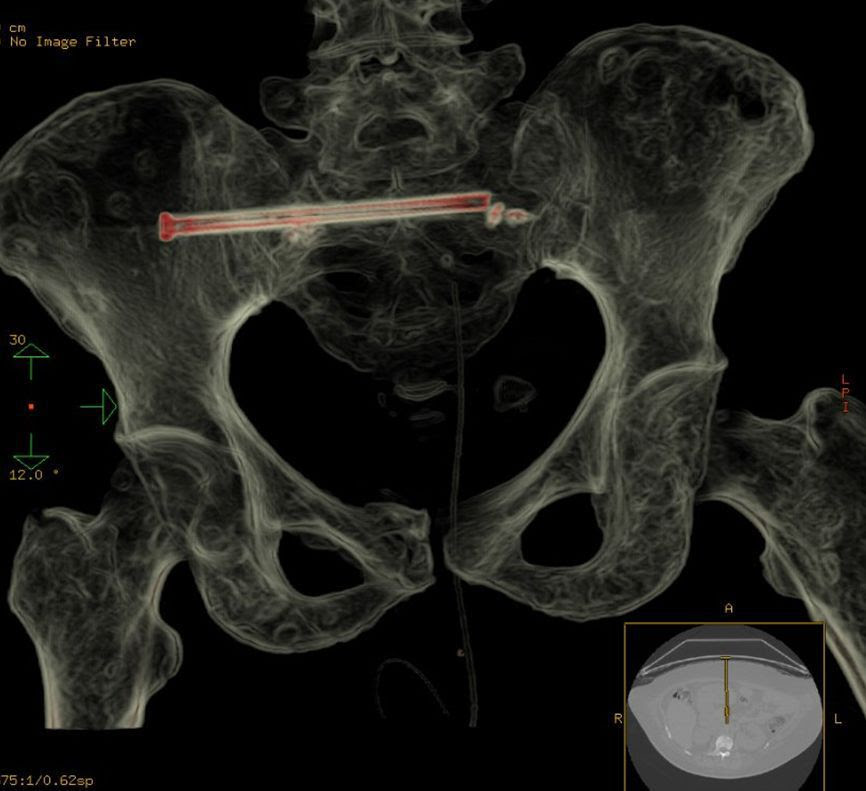

نجح فريق طبي متخصص بمدينة الملك فهد الطبية في تثبيت كسر في العظم العجزي بمنطقة الحوض لمريضة سرطان عن طريق وضع مسمار معدني طبي باستخدام الأشعة التداخلية دون جراحة.

وأوضح تجمع الرياض الصحي الثاني أن المريضة المصابة بسرطان الثدي من الدرجة الرابعة والذي وصل للعظام تعاني من آلام في أسفل الظهر ولديها صعوبة كبيرة بالقيام والجلوس، وبعد عمل الأشعة والفحوصات اتضح أن لديها كسور في أكثر من منطقة من ضمنها منطقة الحوض.

وأوضح استشاري أشعة العظام والعضلات والأشعة التداخلية اللاوعائية أن الطريقة المثلى لعلاج مثل هذه الآلام هي تثبيت الكسر لتخفيف الألم وتسهيل عمل تمارين التأهيل للمريضة، لافتا أن هذه التقنية بدأت قبل سنوات وأثبتت نجاحها للمرضى الذين لا يحتاجون الجراحة أو يصعب القيام بها بسبب حالتهم الحرجة كمرضى هشاشة العظام. موضحاً أن الإجراء يتم عن طريق فتحة في الجلد من 2 إلى 3 ملم تحت التخدير الموضعي أو العام، وتستغرق قرابة الساعتين في الجلسة واحدة.